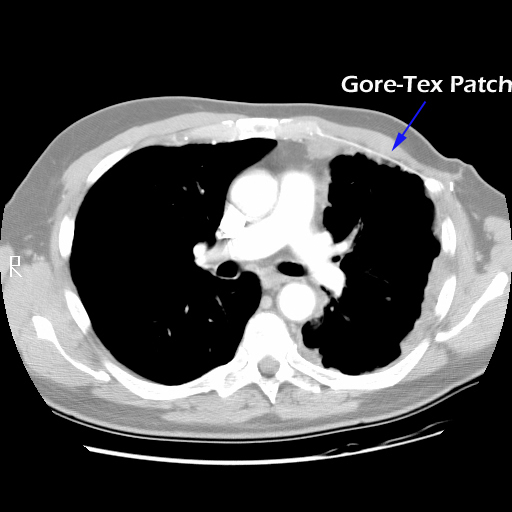

Eleven months later, he presented with a several month history of a painful fixed, firm mass over the pectoral area of the left chest and a smaller mass inferior to this (Figure 1). CT scan demonstrated a new 2 cm nodule in the left upper lobe associated with an anterior chest wall mass six centimeters in size in addition to bilateral new pulmonary nodules (Figure 2). The mass was tethered to the skin and in danger of eroding through it. The patient underwent en-bloc resection of the chest wall and adjacent lung (Figures 3a-c). The resulting defect (Figure 4a) was reconstructed with 2 mm Gore-Tex patch (Figure 4b) and pectoralis major muscle flap (Figure 4c) with primary skin closure (Figure 4d). The pathology revealed metastatic chordoma (Figures 5a-d). The patient recovered well, leaving the hospital on the sixth postoperative day.

The appropriate treatment for chest wall metastases for chordoma is not known due to the rarity of this occurrence. Indications for chest wall metastasectomy include resection for diagnosis, local control, and palliation / prevention of skin ulceration and rarely for cure or as part of a multidisciplinary approach [7]. While radiation therapy is another option for local control, its ability to prevent progression of disease is unpredictable and unknown in the case of chordoma. Once the area of the chest wall has been irradiated, subsequent resection and reconstruction is more difficult and prone to failure [8, 9]. In the presented case, resection was performed for local control, pain relief and to prevent the complications of ulceration, necrotizing infection and bleeding from a tumor eroding through the anterior chest wall. The principles of chest wall resection were adhered to by performing a full thickness en-bloc resection of the mass, reconstruction with a two mm Gore-Tex patch and coverage with a well-vascularized myocutaneous flap.